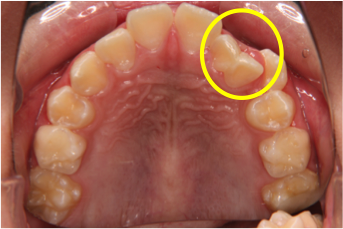

歯の数が足りないのと逆に、余分な歯がある場合もあります。これは「過剰歯」といいます。上の前歯の付近によく見られますが、生えてくるまで気づかないことが多く、また、過剰歯があるために正常な歯が生えてこないことがよくあるため、たまたま撮影したレントゲンによって発見されることではじめて気づくことが多く知らないうちに歯並びや隣の歯に影響が出ます。(図5、6、7)

図5:上の前歯の間にある過剰歯